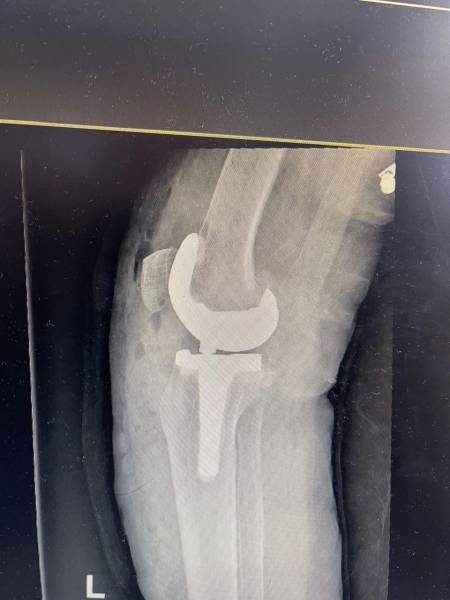

- إجراء عمليات جراحية معقدة و دقيقة في مجال العظام و المفاصل و الكسور و الإصابات ، رغم الضغط الكبير على المستشفى و أعداد المراجعين الكبيرة.

- تطبيق تقنيات جراحية حديثة و متقدمة، و ذلك في ظل التحديات التي يواجهها الفريق بسبب أعداد المرضى و المراجعين الكبيرة.